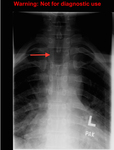

The "winking owl" sign (arrow): asymmetric appearance of spine on plain radiographs caused by destruction of the pedicle

Created by BMJ Publishing Group